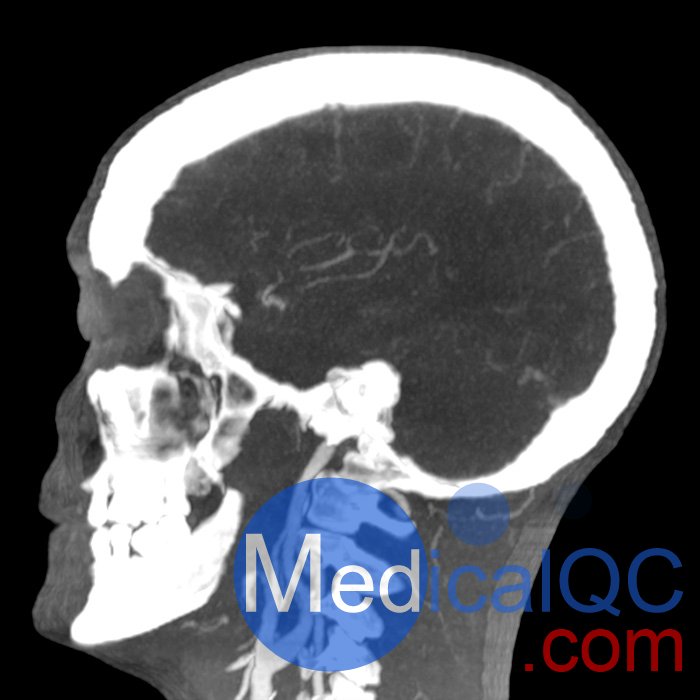

phantomX頭頸部模型,phantomX頭部模體是根據(jù) CT 數(shù)據(jù)制造的,包括所有組織的解剖細(xì)節(jié)。它經(jīng)過(guò)優(yōu)化,可在計(jì)算機(jī)斷層掃描中以 120 kVp 成像提供真實(shí)的衰減值,對(duì)應(yīng)于 73 keV 的平均光譜能量。可根據(jù)要求校準(zhǔn)其他光譜能量。

體模的尺寸和設(shè)計(jì)可能會(huì)發(fā)生細(xì)微變化。體??梢宰鳛橐患綌M人體?;蛞越孛嬖O(shè)計(jì)的形式提供。可以包括病理特征(例如,腫塊、血管病變)。